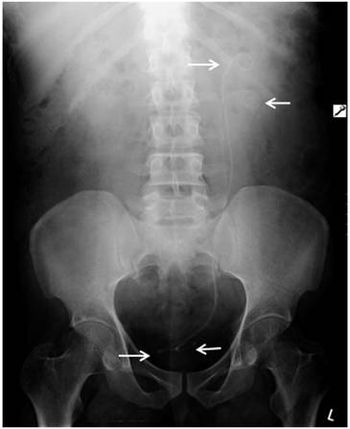

It’s been argued that repeat/reject analysis, a quality-assurance tool to observe trends and make improvements that help reduce the need for repeat images, is not necessary when using digital equipment. While it is true that digital imaging reduces some error rates, the results on the Mayo Clinic digital poster exhibit at the RSNA meeting showed that mistakes still occur in the digital environment.